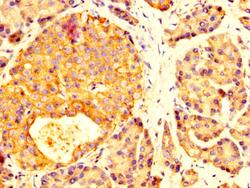

- Submitted by

- Invitrogen Antibodies (provider)

- Main image

- Experimental details

- Immunohistochemical analysis of MYOC in paraffin embedded human pancreatic tissue using a MYOC polyclonal antibody (Product # PA5-98815) at a dilution of 1:200. After dewaxing and hydration, antigen retrieval was mediated by high pressure in a citrate buffer (pH 6.0). Section was blocked with 10% normal goat serum 30min at RT. Then primary antibody (1% BSA) was incubated at 4°C overnight. The primary is detected by a biotinylated secondary antibody and visualized using an HRP conjugated SP system.